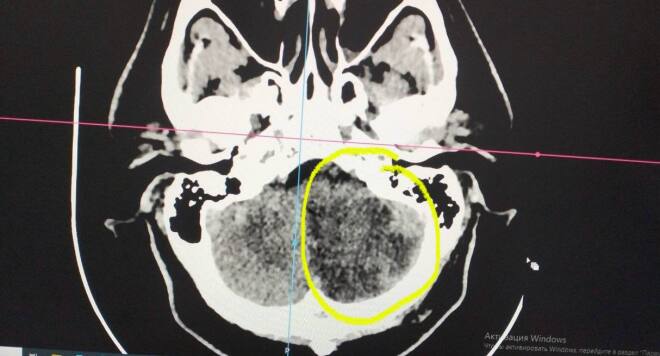

История, которая заставляет задуматься и изменить приоритеты. Пациент 1983 года рождения — не пенсионер, а человек в самом расцвете сил. Он обратился в больницу с, казалось бы, обычными жалобами: высокое давление и головная боль. Но за несколько часов все превратилось в интенсивное головокружение, неукротимую рвоту. Диагноз: обширный ишемический инсульт левого полушария мозжечка.

Его мозг атаковала катастрофа, которая раньше считалась уделом пожилых. 10 суток в реанимации, борьба за жизнь, сосудистая терапия — и лишь через полторы недели состояние удалось стабилизировать.